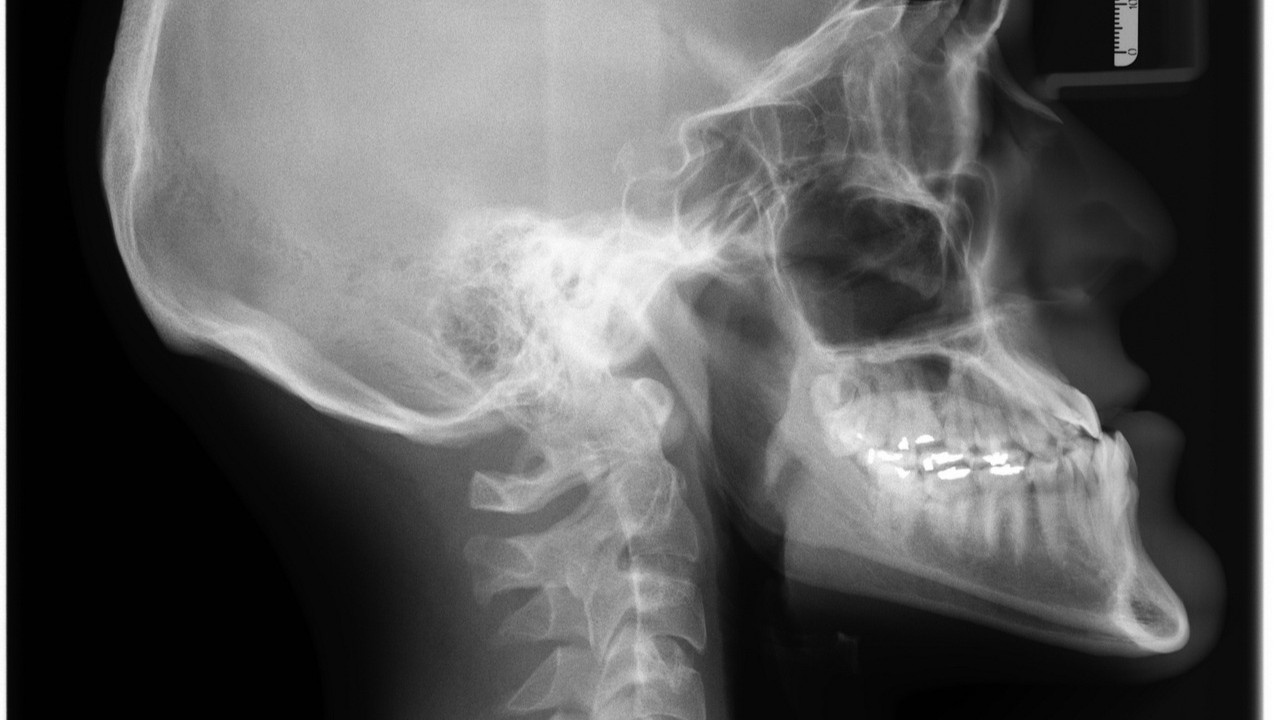

顎骨は顔の形を支えるだけでなく、咀嚼や発声といった基本的な生命活動に不可欠な役割を担っています。

特に歯を支える歯槽骨を含むため、歯科治療やインプラント治療との関わりも深い骨です。

この顎骨は単なる石灰化組織ではなく、血管や神経が複雑に走行し、筋肉や軟組織との相互作用を通じて成長や修復を繰り返す動的な構造を持っています。